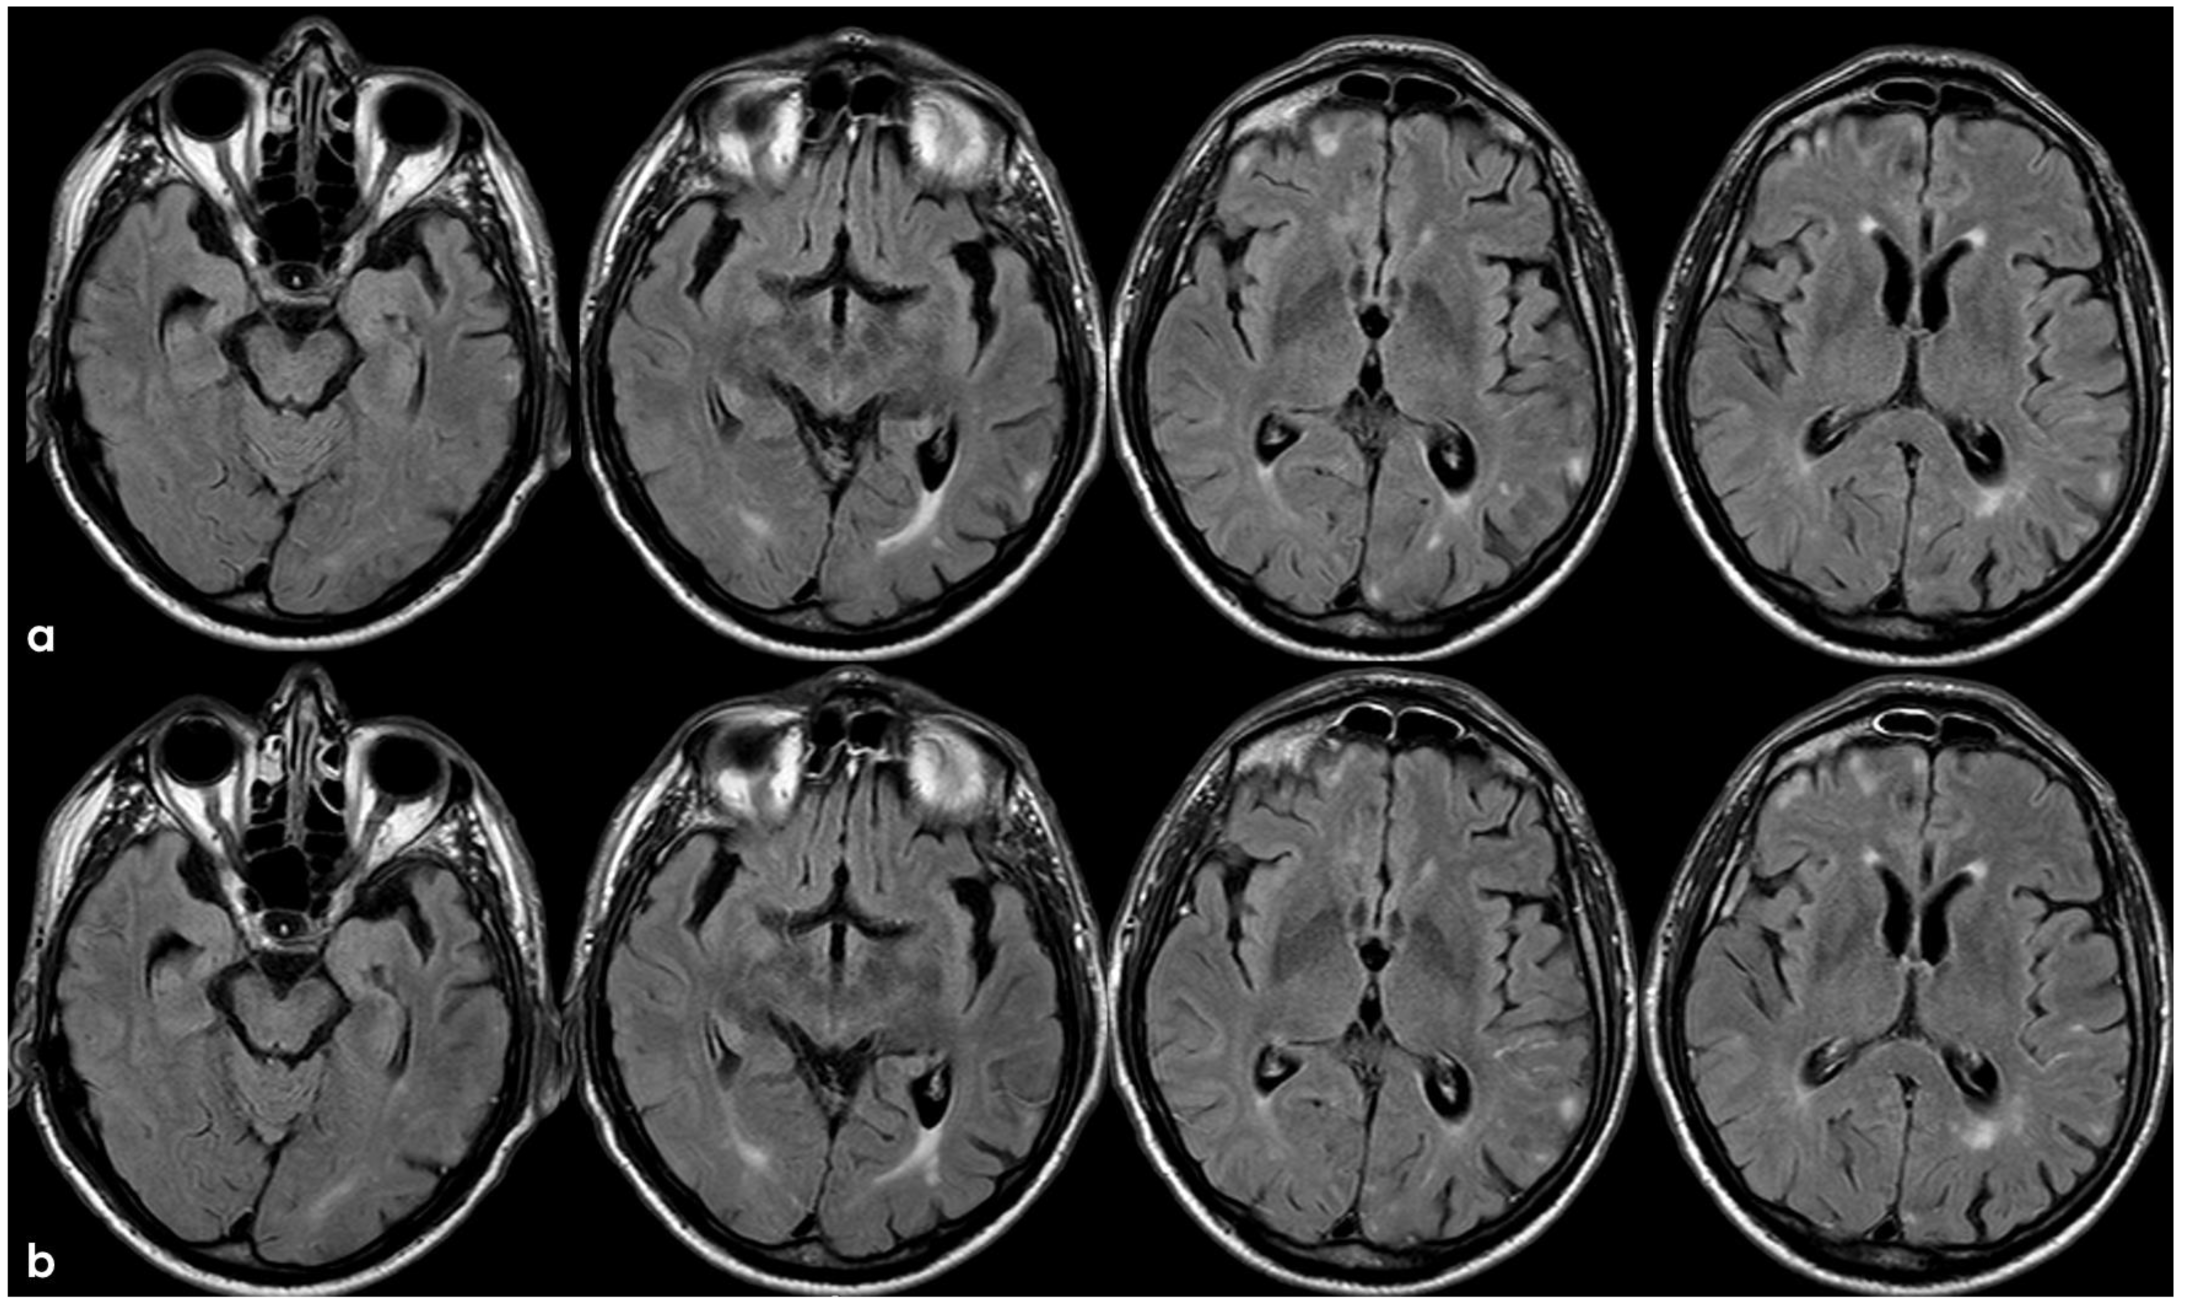

3. May 2014: CAA-Related Inflammation

5. February 2017: First Recurrent CAA-Related Inflammation

7. April 2018: Second Recurrent CAA-Related Inflammation

8. April 2018: Third Recurrent CAA-Related Inflammation